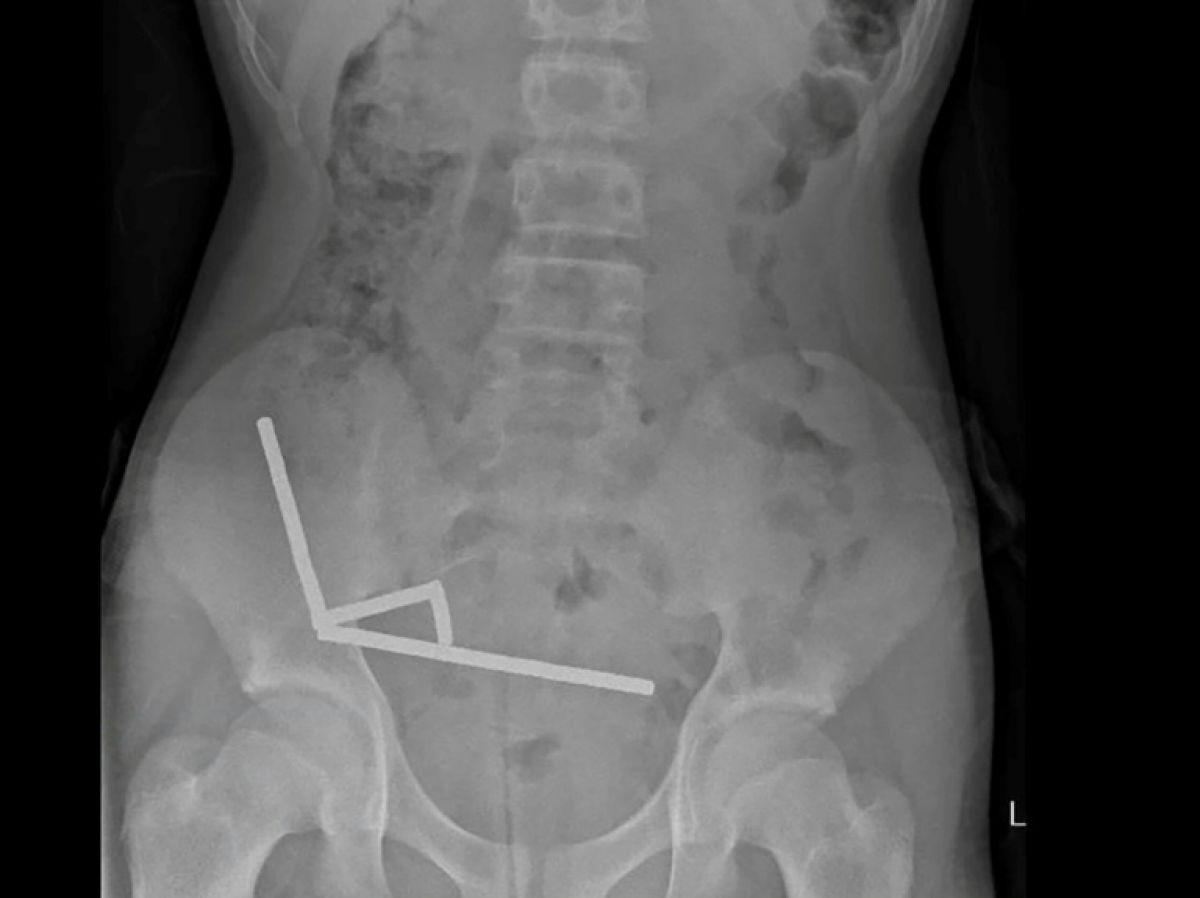

Africa-Press – Congo Brazzaville. Après avoir souffert de douleurs abdominales pendant quatre jours, l’adolescent a été transporté à l’hôpital de Tauranga, sur l’île du Nord. « Il a avoué avoir ingéré entre 80 et 100 aimants puissants au néodyme, de 5x2mm environ, une semaine plus tôt », indique un rapport des médecins de l’hôpital de cet hôpital, publié dans le New Zealand Medical Journal (NZMJ).

Ce type d’aimants, interdit en Nouvelle-Zélande depuis janvier 2013, aurait été acheté sur la plateforme chinoise d’e-commerce Temu. Les médecins ont déclaré que la pression exercée par les aimants avait provoqué une nécrose dans quatre zones de l’intestin grêle et du gros intestin du garçon.

Il a été opéré afin que l’on lui retire les aimants et les tissus nécrosés, et il a pu rentrer chez lui après huit jours à l’hôpital. L’article explique qu’une intervention chirurgicale à la suite de l’ingestion d’aimants peut entraîner des complications, telles qu’une obstruction intestinale, une hernie abdominale et des douleurs chroniques.